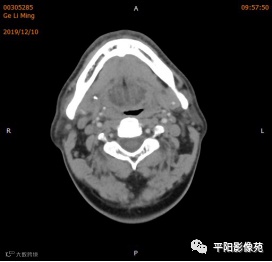

双侧颌下腺、腮腺对称,形态完整,右侧颌下腺强化程度较左侧略低,其内涎腺管增粗,周围脂肪间隙清晰,邻近骨质未见异常,右侧涎腺走行区可见结节样致密影,较大者大小约0.5cm,双侧颌下软组织对称,未见异常密度,所扫范围颈部未见明显肿大淋巴结。

考虑右侧涎腺管结石。

右侧颌下腺强化程度较左侧略低,涎腺管扩张,考虑炎性改变,请结合临床。